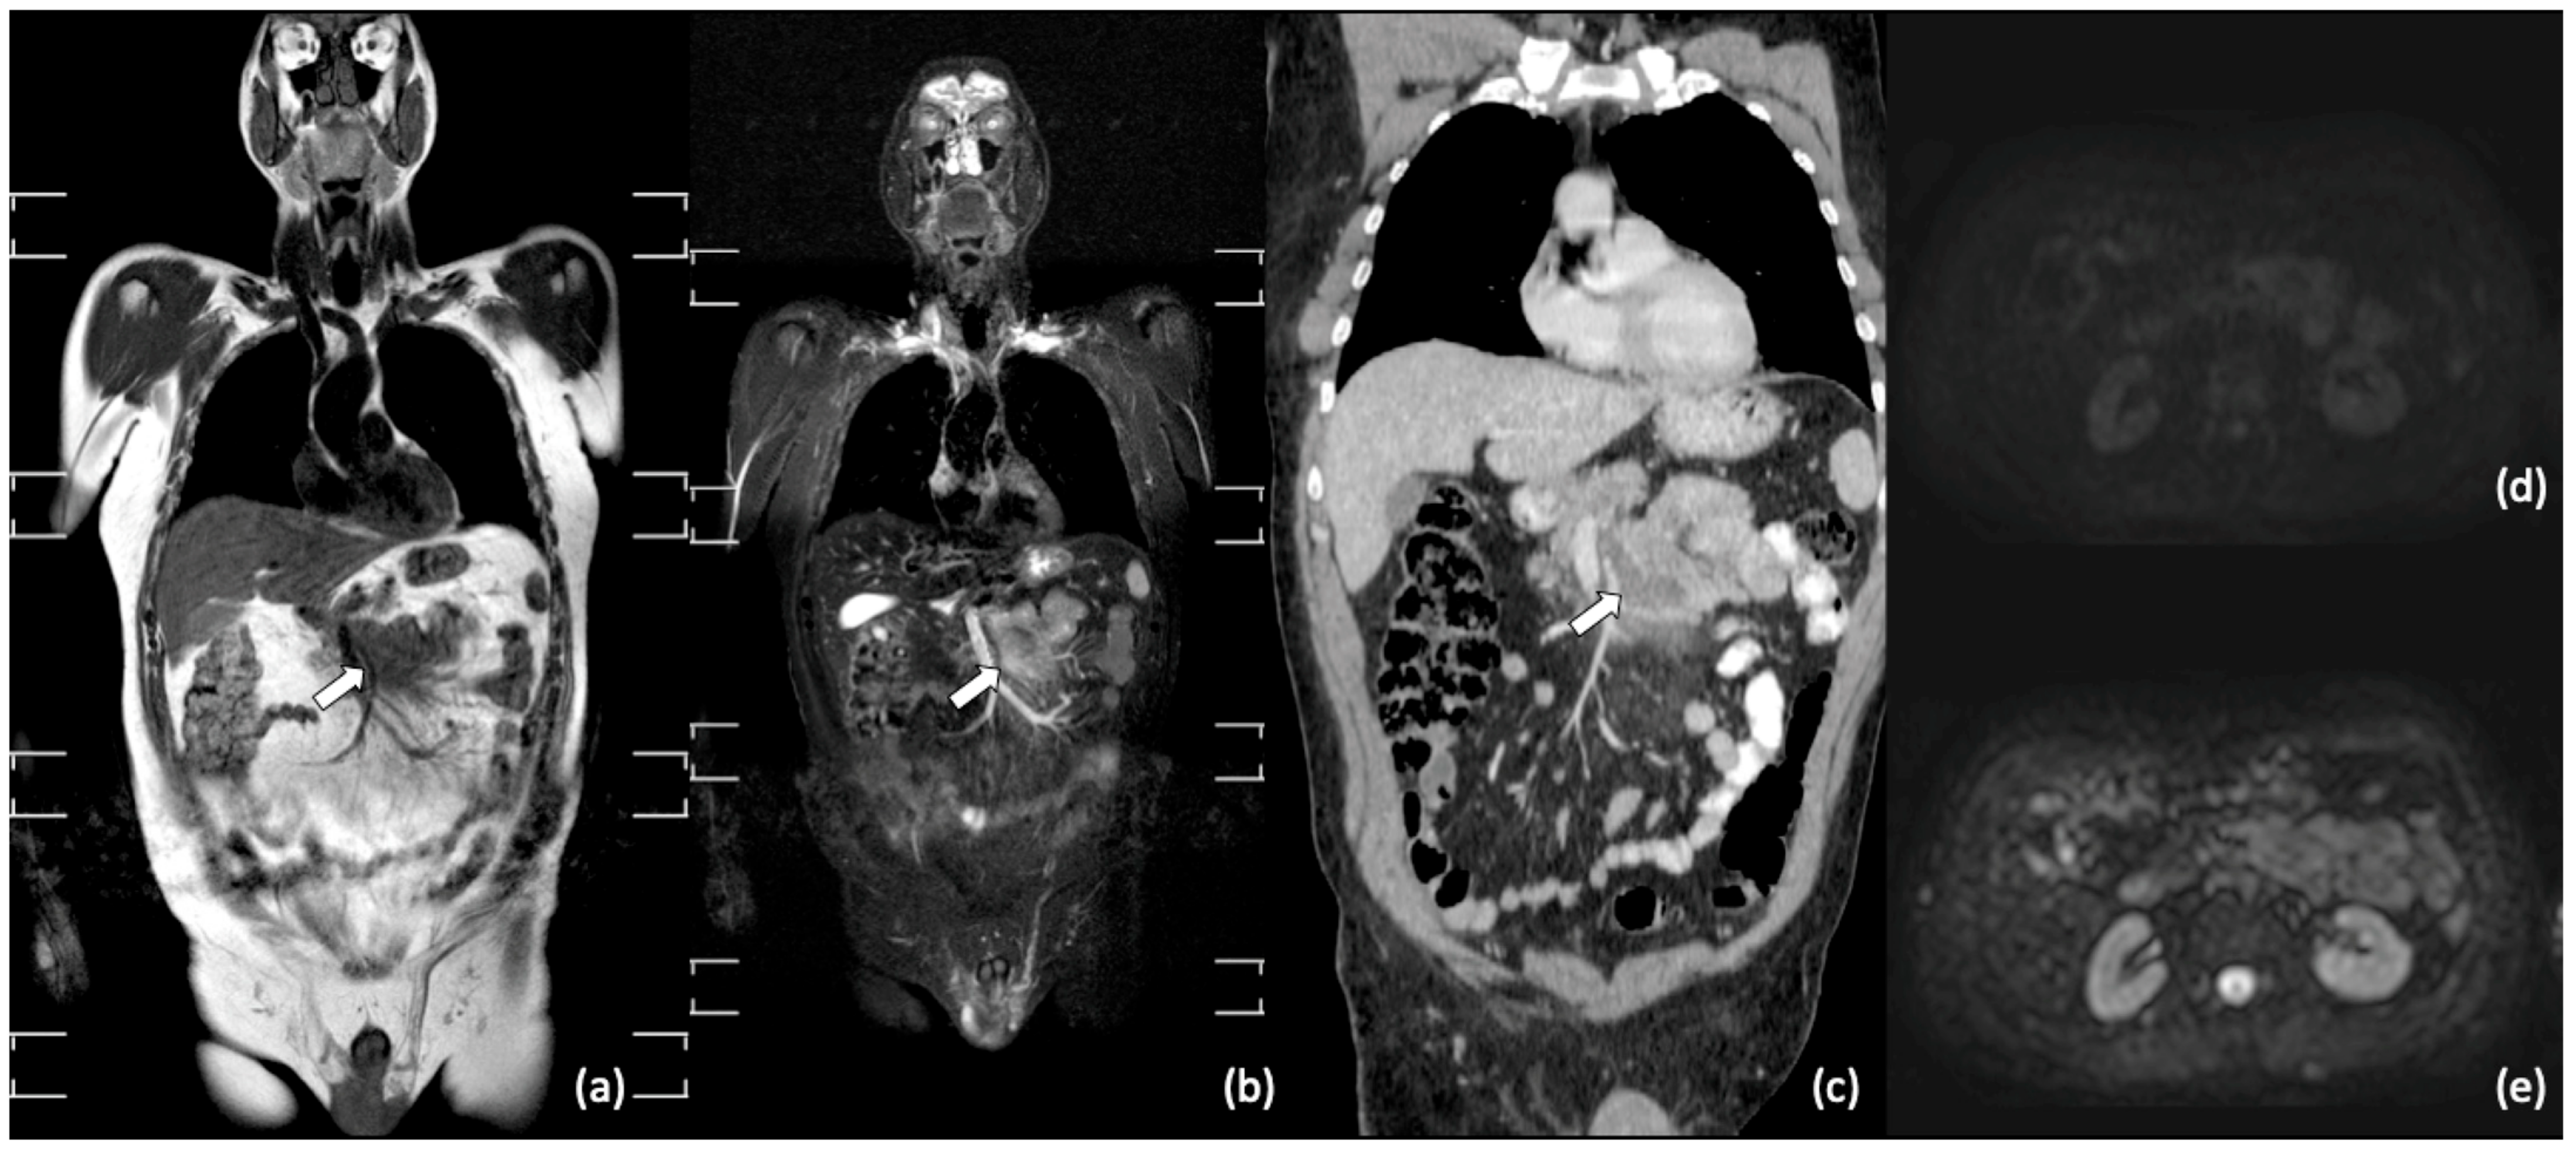

- Kwee, T.C.; Vermoolen, M.A.; Akkerman, E.A.; Kersten, M.J.; Fijnheer, R.; Ludwig, I.; Beek, F.J.; van Leeuwen, M.S.; Bierings, M.B.; Bruin, M.C.; et al. Whole-body MRI, including diffusion-weighted imaging, for staging lymphoma: Comparison with CT in a prospective multicenter study. J. Magn. Reson. Imaging 2014, 40, 26–36. [Google Scholar] [CrossRef]

- Balbo-Mussetto, A.; Cirillo, S.; Bruna, R.; Gueli, A.; Saviolo, C.; Petracchini, M.; Fornari, A.; Lario, C.; Gottardi, D.; De Crescenzo, A.; et al. Whole-body MRI with diffusion-weighted imaging: A valuable alternative to contrast-enhanced CT for initial staging of aggressive lymphoma. Clin. Radiol. 2016, 71, 271–279. [Google Scholar] [CrossRef] [PubMed]

- Stecco, A.; Buemi, F.; Quagliozzi, M.; Lombardi, M.; Santagostino, A.; Sacchetti, G.M.; Carriero, A. Staging of Primary Abdominal Lymphomas: Comparison of Whole-Body MRI with Diffusion-Weighted Imaging and18F-FDG-PET/CT. Gastroenterol. Res. Pr. 2015, 2015, 1–8. [Google Scholar] [CrossRef] [PubMed]

- Stecco, A.; Trisoglio, A.; Soligo, E.; Berardo, S.; Sukhovei, L.; Carriero, A. Whole-Body MRI with Diffusion-Weighted Imaging in Bone Metastases: A Narrative Review. Diagnostics 2018, 8, 45. [Google Scholar] [CrossRef] [PubMed]

- Adams, H.J.A.; Kwee, T.C.; Vermoolen, M.A.; De Keizer, B.; De Klerk, J.M.H.; Adam, J.A.; Fijnheer, R.; Kersten, M.J.; Stoker, J.; Nievelstein, R.A.J. Whole-body MRI for the detection of bone marrow involvement in lymphoma: Prospective study in 116 patients and comparison with FDG-PET. Eur. Radiol. 2013, 23, 2271–2278. [Google Scholar] [CrossRef] [PubMed]